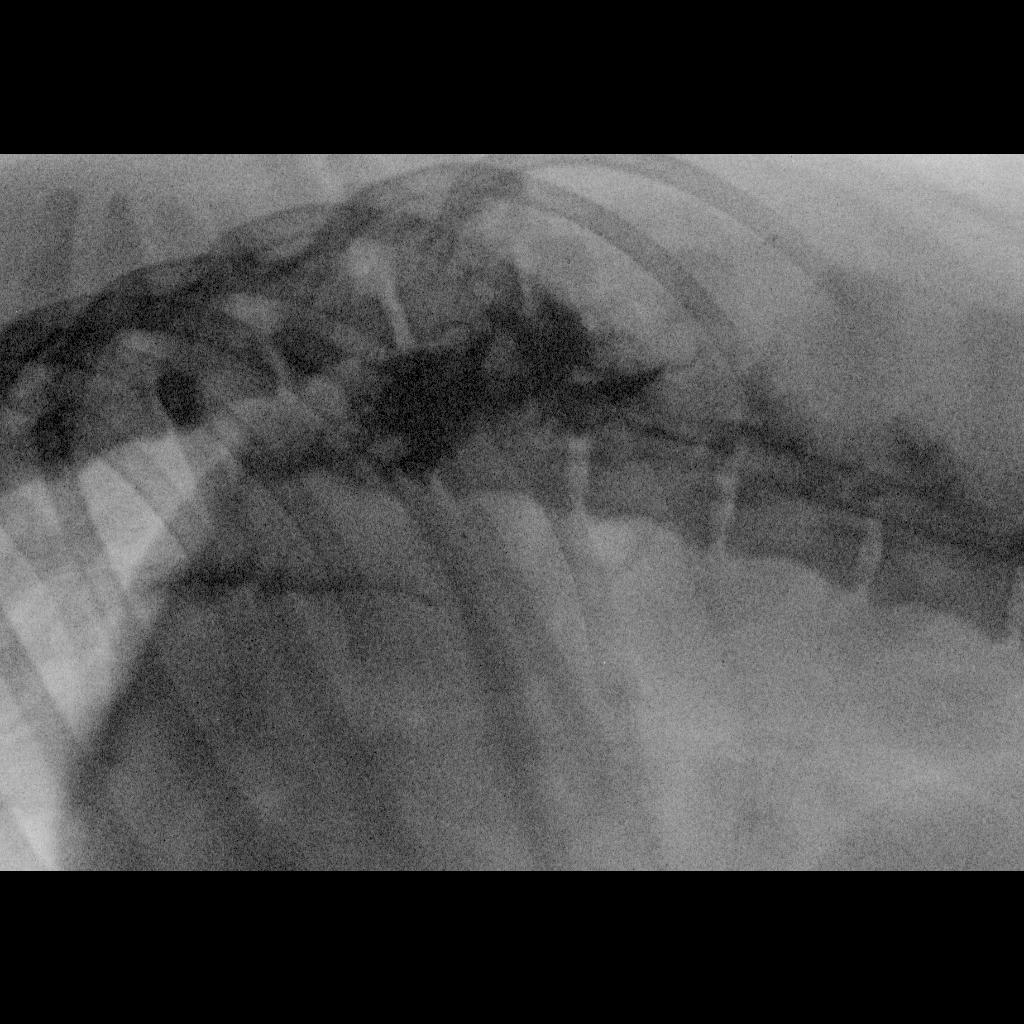

Pet's info: Dog | Labrador Retriever | Male | unneutered | 3 years and 10 months old | 75 lbs

Hi, My 4 year old black lab had a bike accident. The mylogram shows overriding fracture at T13-L1 of his spine. Even though his very has suggested euthanasia, I want to give him a chance. Could you please tell me if keeping him alive would lead to medical complications or would have serious effects on his health? I am willing to put in all the hardworkd required to keep him happy, unless euthanasia is the only way.

Hi and thank you for your post. While surgery may be possible, this should be done at a specialty or veterinary teaching hospital at a University for sure. It is highly likely Jordan will have multiple neurological deficits after surgery and make never be able to use his legs normally. He may have problems defecating and urinating. The road for recovery will be long and arduous for both you and Jordan. He will need lots of physical rehabilitative therapy and constant round the clock care for quite some time. How long will depend on his response to treatment, therapy and medication. Best to you and Jordan! Thank you for using Petco Pet Education Center, formerly Petcoach!